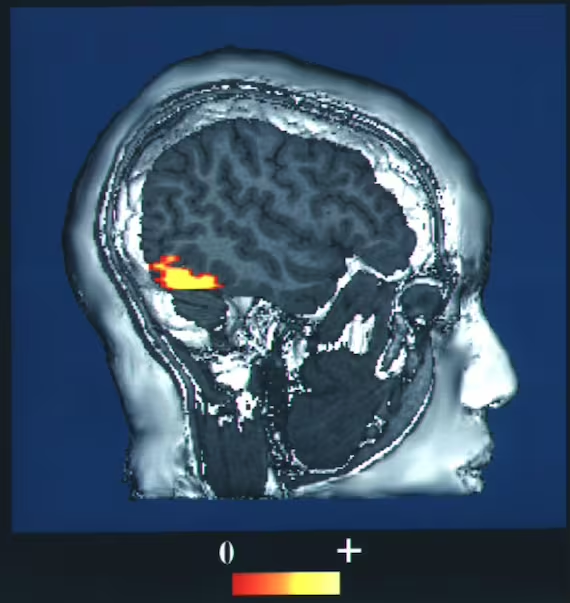

Le indagini strutturali e funzionali hanno confermato il coinvolgimento di aree cerebrali specifiche. La risonanza magnetica (MRI) e la PET (Tomografia ad Emissione di Positroni) mostrano spesso atrofia o ipometabolismo in regioni chiave:

- lobo frontale e regioni sottocorticali: alterazioni bilaterali dei centri semiovali, spesso associati all’emozione del disgusto e a circuiti simili a quelli del disturbo ossessivo-compulsivo;

- emisfero destro: esiste una forte correlazione tra lesioni del lato destro (92% dei casi di DMS) e lo sviluppo di deliri di identificazione, a causa della lateralizzazione dei processi di riconoscimento facciale e monitoraggio spaziale;

- corteccia retrospleniale: coinvolta nella percezione della familiarità; lesioni in quest’area impediscono il corretto collegamento tra oggetti percepiti esternamente e rappresentazioni interne recuperate dalla memoria;

- giro fusiforme destro: spesso atrofico nei pazienti con Alzheimer che manifestano Capgras, suggerendo una degradazione dei moduli di elaborazione visiva complessa.

- MRI cerebrale: indispensabile per rilevare atrofia focale, lesioni del lobo frontale destro o alterazioni dei lobi temporali;

- FDG-PET: mostra un ipometabolismo corticale diffuso e una marcata disfunzione frontale destra, specialmente nelle fasi precoci di DLB e AD;